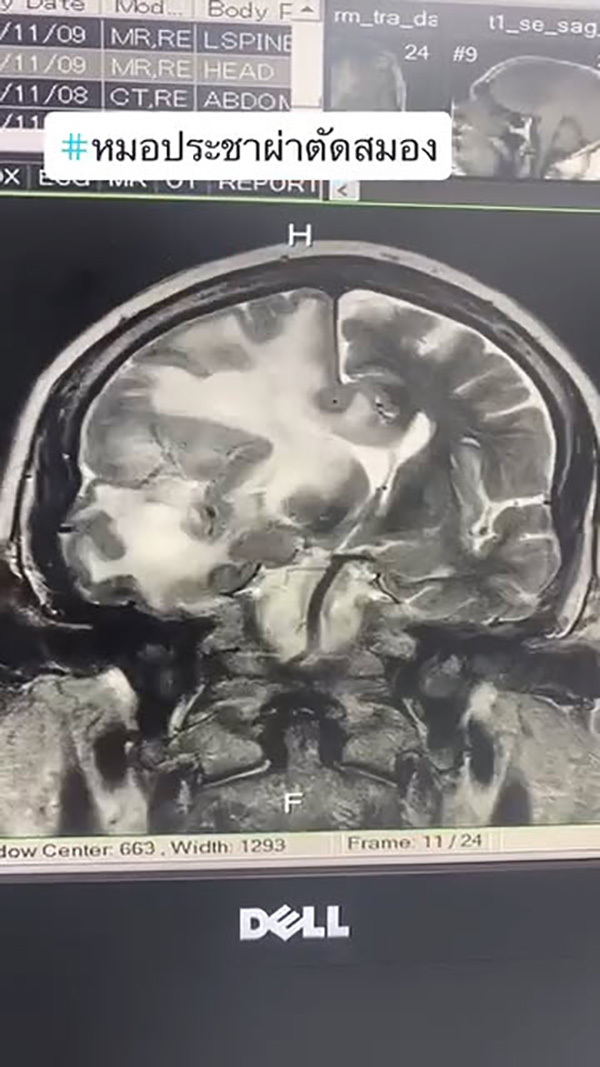

ปวดหัวอาการแบบไหน สงสัยว่าเป็นเนื้องอกสมอง พร้อมยกเคสอาการปวดหัวของผู้ป่วยชาย ชาวต่างชาติ อายุ 70 ปี มาโรงพยาบาลด้วยอาการปวดหัวนาน 2 สัปดาห์ เอกซเรย์สมองพบก้อนเนื้องอก สมองบวมมาก เคสนี้ผ่าตัดก้อนเนื้องอกออก ไม่อันตราย ผ่าตัดแล้วหาย

ภาพจาก เฟซบุ๊ก หมอประชาผ่าตัดสมอง